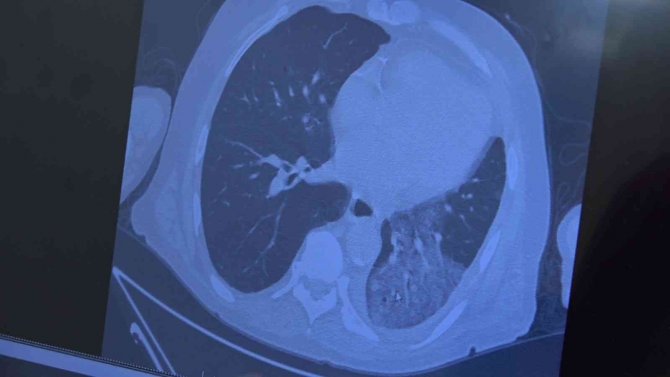

Açıklamalarda bulunan Prof. Dr. Özkaya, "Bilindiği gibi vaka sayılarında ciddi azalmalar var. Yatan hasta sayılarında ve yoğun bakım sayılarımız yok denecek kadar azaldı. Bu hala virüsün doğadan kaybolduğunu göstermiyor. Salgının sonuna geldik ama hastalık hala geliyor. Yine tek tek hastalarımız gelmeye başladı. Özellikle önümüzde bayramda maske yasağının gevşetilmesi, havaların ısınmasıyla insanlar özlenen hayatlarına geri dönecekler. Bayramdan sonra bir miktar vaka sayılarında artış bekliyoruz. Gerçekten şuan normal vakalar zatürre vakaları seviyesindedir. Artık salgının topluma getirdiği ekstra bir risk yoktur. Alarm durumunda dikkat etme durumuna geçtik. Özellikle bu yurt dışı turlarının etkisiyle bayramla birlikte ve bayramdan sonra vaka artışları bekliyoruz. İnsanlarımızın mevcut aşılarına, mevcut kontrollü sosyal hayatlarına devam etmelerini öneriyoruz. Her ne kadar toplumda şu an yatan hasta sayısı olmasa da özellikle 65 yaş ve üstü hastalarımızda, immün sistemi düşük hastalarımız akciğer tutulumlarıyla gelmeye başladı. Bunun bayramdan sonra artmaması için yaşlılarımızı bayramda ziyaret ederken lütfen onlara kontrollü yaklaşmanızı istiyoruz" diye konuştu.